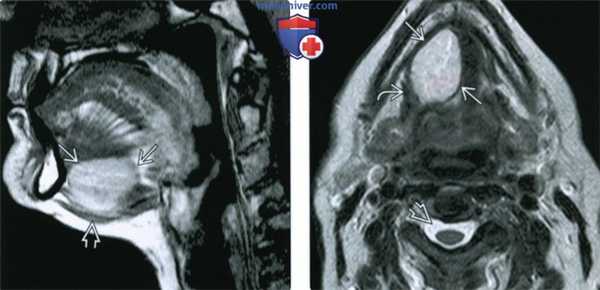

(Слева) МРТ Т1ВИ, сагиттальная проекция, эпидермоидная киста с гиперинтенсивным сигналом, происходящая из передних отделов корня языка и смещающая вниз мышцы дна полости рта. Гиперинтенсивный сигнал говорит в пользу высокого содержания белка.

(Справа) МРТ Т2ВИ, аксиальная проекция, тот же пациент. Неоднородный сигнал умеренно высокой интенсивности. Из-за высокого содержания белка сигнал гипоинтенсивный относительно ликвора. Вдоль латеральной границы образования проходит челюстно-подъязычная мышца.